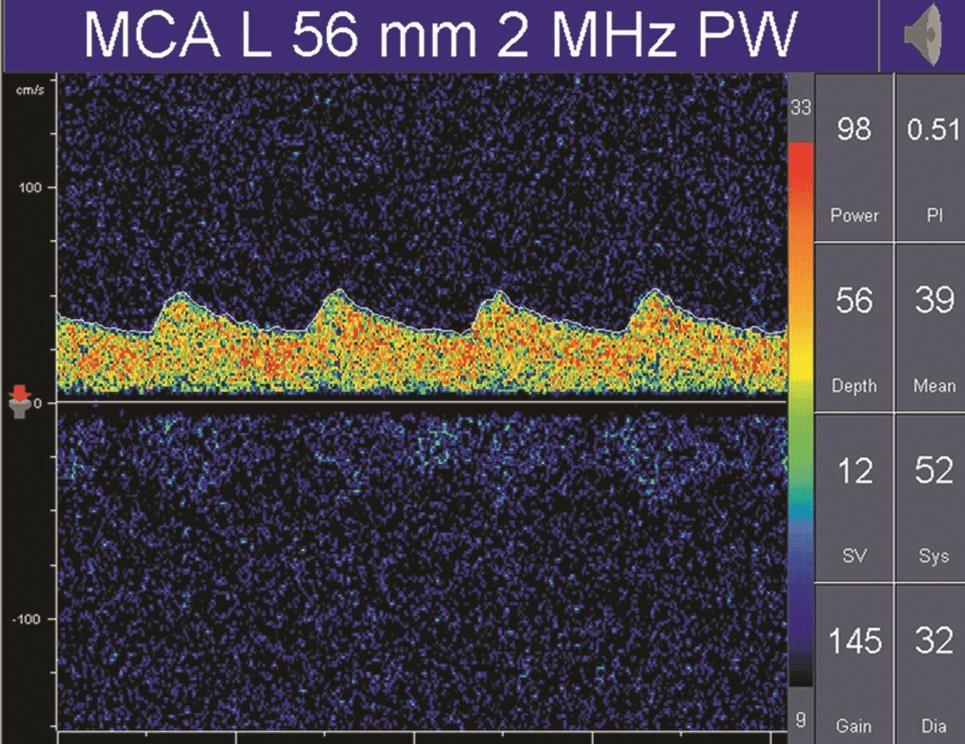

在病理情況下,低阻力頻譜可見于動靜脈畸形供血動脈、大動脈嚴(yán)重狹窄或閉塞后遠(yuǎn)端灌注明顯不足的血管內(nèi)血流及開放的側(cè)支循環(huán)(詳情見下圖);

而高阻力頻譜則見于顱內(nèi)壓增高、大動脈嚴(yán)重狹窄或閉塞的近端血管,以及長期高血壓受檢者(詳情見下圖)。